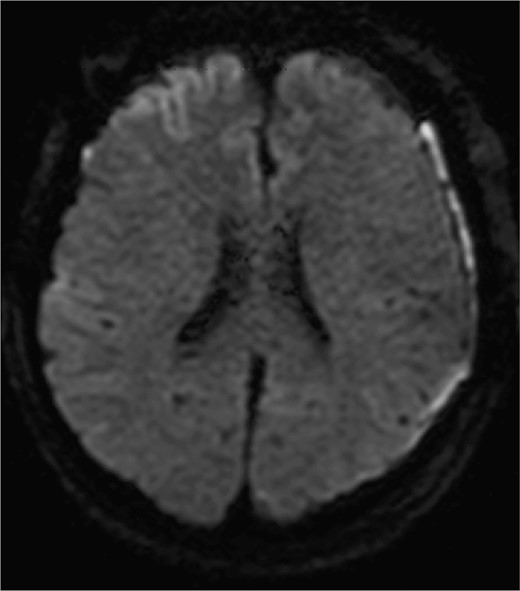

Diffusion-weighted images on postoperative day 3 are shown. No obvious ischemic changes are seen.

Given the uncertainty regarding the rupture site, we first performed left frontotemporal craniotomy, which confirmed an unruptured ICA aneurysm. Subsequently, bilateral frontal craniotomy was performed with careful evacuation of the SDH. The callosomarginal artery was readily identified in a relatively shallow subarachnoid space during interhemispheric fissure dissection. No SAH was observed. The aneurysm body demonstrated strong adhesion to the left side of the falx cerebri, with white thrombus continuous with the SDH, identifying it as the rupture site. Both the left ICA and DACA aneurysms were successfully clipped. Postoperative diffusion-weighted imaging on day 3 showed no frontal cortical ischemic changes (Fig. 3). DACA flow without vasospasms was confirmed by cerebral angiography on day 8. The patient was discharged without neurological deficits.